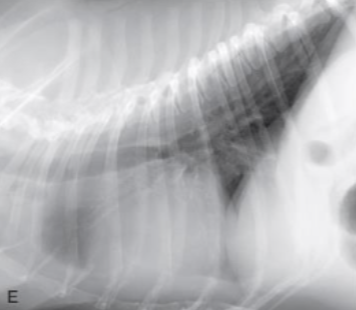

| 2) ==RCHF== |

| lung, PA โ RV โ RA โ CVC โ peritoneum |

| ๊ธฐ์ ์ฐ์ฌ์ค์์ ํ๋๋งฅ์ผ๋ก ํ์ก์ ์ถฉ๋ถํ ๋ด๋ณด๋ด์ง ๋ชปํด, ์ฐ์ฌ๋ฐฉ๊ณผ ์ฒด์ํ ์ ๋งฅ์ ํ์ก์ด ์ ์ฒด๋จ. |

| ์์ธ - ์ข์ฌ๋ถ์ โ ํ๊ณ ํ์ โ ์ฐ์ฌ์ค ๊ณผ๋ถํ โ ์ฐ์ฌ๋ถ์ ๋ฐ์ - PS, PH, TVI ๋ฑ์ผ๋ก ์ธํด ๋ฐ์ (=๋ํ ์ง๋ณ) |

| Radiographic signs - RA, RV enlargement - mPA bulging (reversed D) - Bilateral pleural effusion (interlobar fissure, scallop sign.. ๋ฑ) - Ascites, Edema, CVC dilation, Hepatosplenomegaly |